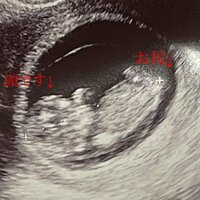

続けて、夫でグラフィックデザイナー・小泉貴之さんにエコー写真を見せ「あなたに似てるよね!?」と問いかけたところ、「分かんない」との返事があったといい「そりゃそうか!?」と納得した様子をみせた。

その後に更新したブログでは「アプリのトツキトオカで、器官がほぼ完成のお知らせ」「骨もだんだん硬くなってきて、顔立ちも はっきりしてきているそうです!」とアプリの情報を基に胎児の状態を説明。